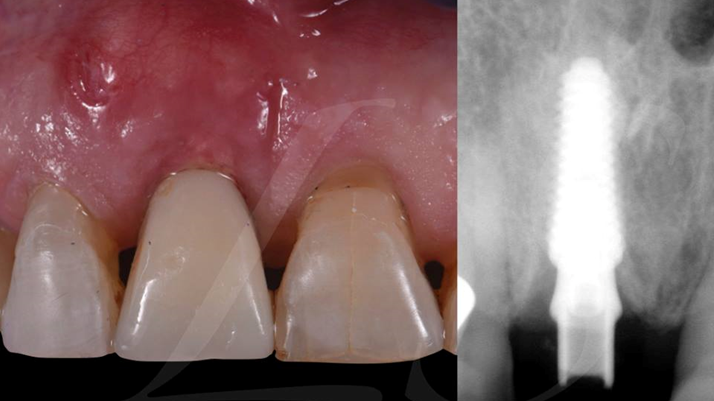

Clinical case: Extraction, immediate placement & loading using

R2GATE solution in aesthetic zone

- Courtesy of Dr. Jong-Cheol Kim, Korea-

Dr. Jong Cheol Kim, immediate loading, digital guided surgery, Digital ONE-DAY Implant, maxillary anterior, #21, guided surgery, immediate loading, AnyRidge, R2GATE, Mega ISQ, MEG Torq, R2GATE Full Surgical Kit

AnyRidge implant system, R2 Guide, R2GATE Full Surgical Kit, Mega ISQ